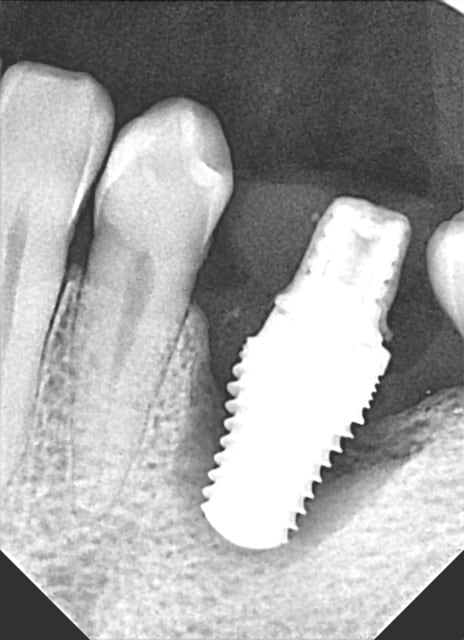

Un dernier pour la route legacy2 7mm

16 RTE 2006 /2007 avec curetage périapical et IRM

échec de cicatrisation et extraction-implantation le26.02.2011

empreinte essayage pose le 24.10.2011

radios de contrôle en 2012 et 2013

patiente revue en 2014 cbct =ok